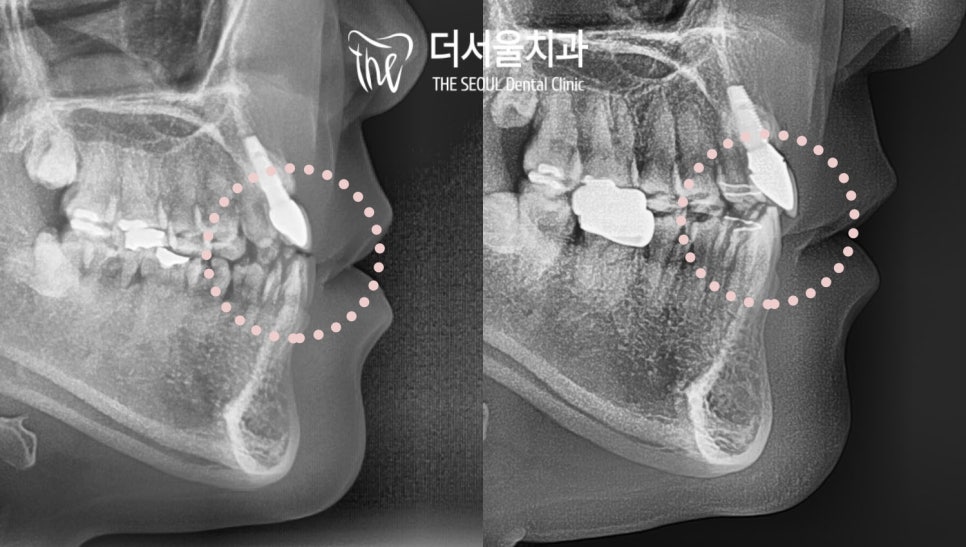

파노라마 엑스레이 사진을 보면

앞니 두 개는 인공치근을 식립했기에

방사선 불투과성의 형태를 띠고 있습니다.

파노라마 사진에서 보면

그 변화를 조금 더 확연하게 관찰할 수 있습니다.

앞니끼리 맞닿거나

윗니보다 아랫니가 앞으로 튀어나와 있는 경향에서

정상교합으로 바뀌었습니다.